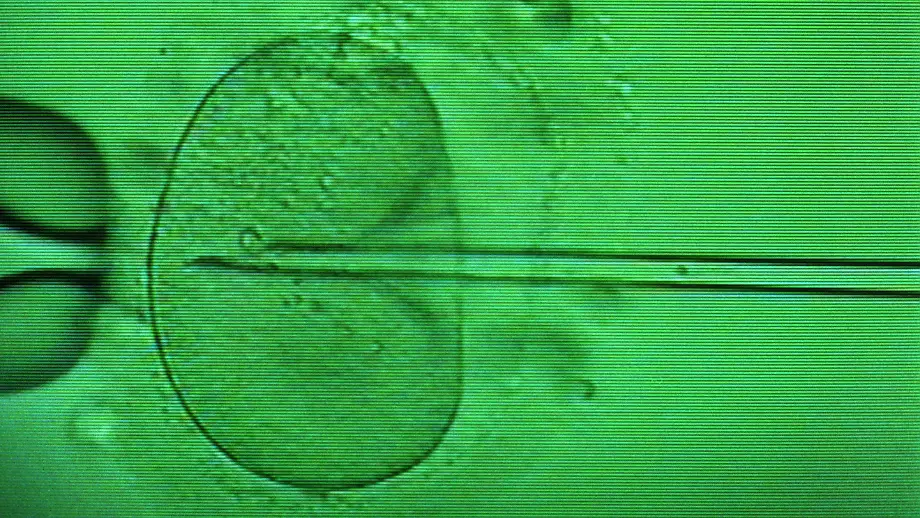

Videontv ohne Werbung?Jetzt mit dem ntv PUR-Abo: Im 1. Monat kostenlos testen, danach ab 2,99 EUR / Monat.Ihr PUR-Abo auswählenGentests bei EmbryosPID spaltet selbst die CDU-Spitze16.11.2010, 18:15 UhrFacebookXWhatsAppE-MailLink kopierenArtikel druckenTeilenFolgen auf:Videos Meistgesehen05:00 minUSA schießen mit Torpedo"So was hat es seit Zweitem Weltkrieg nicht gegeben"02:47 minMehr Effekt als 10.000 SchritteJapanisches Gehen: Neuer Trend ist perfekt für Sportmuffel01:02 minNeue Drohnen-Taktik zeigt WirkungUkraine trifft russischen Helikopter im Schwarzen Meer00:58 minBlockierte Missbrauchs-VorwürfeFBI-Interviews belasten Trump im Epstein-Skandal schwer00:49 minZuvor alles auf Insta gelöschtRiesen-Schuhe, Mini-Höschen: Megan Fox postet wieder01:37 minEin "Gefühl" als Angriffsgrund?Trump-Sprecherin fetzt sich wegen Iran-Krieg mit Presse01:34 minBillig-Nachfrage sei DankNach Pleite ist Kult-Kaufhauskette zurück auf Erfolgskurs01:07 minOffenbar Iran-Angriff an GolfküsteExplosion reißt Loch in Tanker - Video zeigt Einschlag02:40 minMilitärexperten warnen vor EinmarschFestung Iran: Was eine Boden-Invasion fast unmöglich macht04:29 min"Alzheimer ist kein Schicksal" Experte verrät "Masterplan gegen Demenz"01:58 minSchwester reagierte nicht gutEva Habermann ziert stolz den Playboy02:30 minBröckelnde Allianz mit den USAMarschieren die Kurden bald auf Teheran?01:01 minEines hat er sicher: ZuschauerMcDonald's-Chef isst Burger - Video kassiert endlos SpottTopvideos01:01 minKommission lässt Bürger sprechenTrumps Ballsaal wird zerrissen: "prätentiöses Monstrum"01:40 minFußballlegenden als StatistenTrump nutzt Treffen mit Messi für Todesdrohung an Iraner02:04 minWenn Notaufnahmen überquellenLebensgefahr und kein freies Bett - Krankenhäuser am Limit05:10 minNavidi sieht Gefahren-MixIran-Krieg birgt "Risiko weltweiter Wirtschaftskrise"00:49 minViele Kröten für einen FroschEvelyn Burdecki muss nach Tierrettung ordentlich blechen02:33 minIran-Krieg behindert ReisenWorauf man jetzt bei der Urlaubsplanung achten sollte01:42 minGiftige Produkte nur kurz offlineGreenpeace wirft Shein Schein-Verantwortung vor00:39 minGlibberiger Fund im WasserStand-Up-Paddler findet seltsame Meereskreatur01:46 min"Geld wird gezahlt werden"2000 Unternehmen klagen auf Rückerstattung der Trump-Zölle